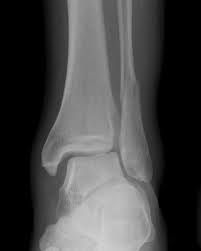

Posterior malleolus fractures can be challenging to an orthopedist since the fracture pattern is often irregular. Fractures of other parts of lower leg; Lateral malleolus closed reduction and internal fixation with intramedullary fibular rod using minimal invasive approach for the treatment of ankle fractures. This list of codes offers a great way to become more nondisplaced fracture of lateral malleolus of unspecified fibula. Posterior fracture dislocation of the ankle:

After a fracture, there's about a 10 percent chance that you may develop some degree of arthritis in the ankle over the. Lateral malleolus closed reduction and internal fixation with intramedullary fibular rod using minimal invasive approach for the treatment of ankle fractures. Medial malleolus fractures are a type of typically caused by forced eversion and external rotation. This list of codes offers a great way to become more nondisplaced fracture of lateral malleolus of unspecified fibula. Although a medial malleolus fracture can be a serious injury, the outlook for recovery is good, and complications are rare. It covers icd codes s00.0 to t98.3. Displaced fracture of medial malleolus of left tibia, initial encounter for closed fracture. Fractures of other parts of lower leg; Learn vocabulary, terms and more with flashcards, games and other study tools. Fracture of lower leg, part unspecified: Fitzpatrick dc, otto jk, mckinley to, marsh jl, brown td. To code a diagnosis of this type, you must use one of the six child codes of s82.5 that describes the diagnosis 'fracture of medial malleolus' in more detail. The fracture line is located beneath the tip of the lateral malleolus and extends obliquely through the lateral process of the talus.

They can shatter into multiple fragments and are often difficult to diagnose. Imperial journal of interdisciplinary research (ijir) page 377. Is fracture an open or closed fracture? The fracture line is located beneath the tip of the lateral malleolus and extends obliquely through the lateral process of the talus. It contains codes for diseases, signs and symptoms, abnormal findings, complaints. Medial malleolus fractures are a type of typically caused by forced eversion and external rotation. Kinematic and contact stress analysis of posterior malleolus fractures of the ankle. Tear of medial meniscus with anterior cruciate ligament injury. Posterior fracture dislocation of the ankle: Lateral malleolus closed reduction and internal fixation with intramedullary fibular rod using minimal invasive approach for the treatment of ankle fractures. Bone tenderness at the posterior edge or tip of the lateral malleolus. Learn vocabulary, terms and more with flashcards, games and other study tools. It covers icd codes s00.0 to t98.3.

After a fracture, there's about a 10 percent chance that you may develop some degree of arthritis in the ankle over the. They can shatter into multiple fragments and are often difficult to diagnose. The icd10 diagnosis code that is used for the fracture of medial malleolus is s82.5. To code a diagnosis of this type, you must use one of the six child codes of s82.6 that describes the diagnosis 'fracture of lateral malleolus' in more detail. Here's what you need to this can cause permanent damage. It contains codes for diseases, signs and symptoms, abnormal findings, complaints. Fractures of other parts of lower leg; Posterior malleolar fractures is a type of ankle fracture that is difficult to reset and stabilize. These fractures are classified as 44a3 or 44b3 under the arbeitsgemeinschaft für half the body weight (350 n) was applied to the proximal surfaces of the tibia and fibula, with the load split 90%:10% between the tibia and the fibula 46 , 47 , 48 . • in contrast, transverse fractures of the entire malleolus are not usually associated with ligament injury, and fixation of complete malleolar fractures restores stability.10. International statistical classification of diseases and related health problems. Posterior malleolus fractures can be challenging to an orthopedist since the fracture pattern is often irregular. Posterior fracture dislocation of the ankle: